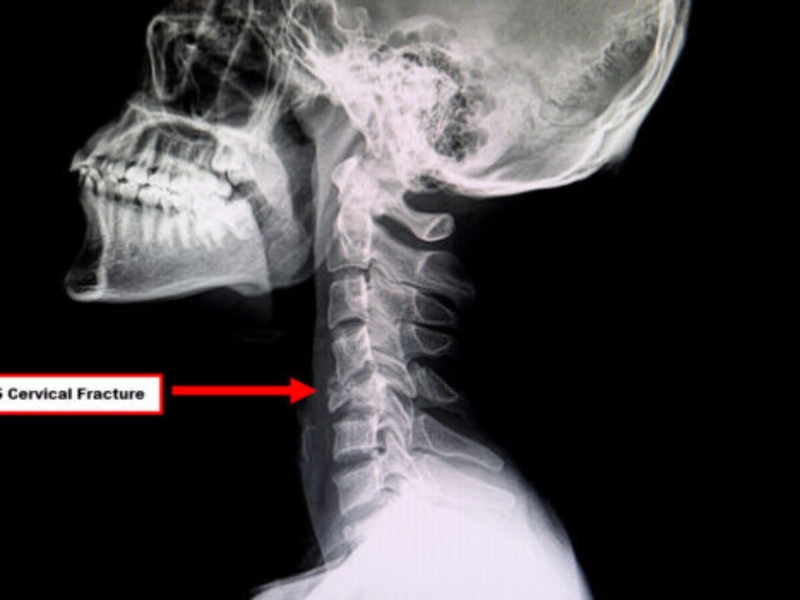

Cột sống cổ được cấu tạo bởi 7 đốt sống đầu tiên, uốn thành hình chữ C. Có thể được chia thành 2 phần là cột sống cổ cao và cột sống cổ thấp. Trong đó cột số cổ cao gồm có 2 đốt sống đầu tiên, đốt số một được gọi là đốt đội, đốt số hai gọi là đốt trục. Hai đốt này có rất nhiều trục xoay và cấu tạo khác biệt so với những đốt còn lại. Cột sống cổ thấp thì gồm 5 đốt sống còn lại với cấu tạo tương tự nhau gồm thân đốt sống phía trước và cung đốt sống phía sau.

Bất kỳ tổn thương nào ở đốt sống cổ cũng có thể gây ra hậu quả nghiêm trọng bởi chúng có tủy sống chạy qua lõi và đảm nhận nhiệm vụ kết nối hệ thống thần kinh trung ương giữa bộ não với toàn bộ cơ thể. Tổn thương ở tủy sống có thể dẫn đến tê liệt hoặc tử vong vô cùng nguy hiểm. Gãy xương cổ hay gãy đốt sống cổ là tình trạng nứt vỡ của bất kỳ một trong bảy đốt sống ở cổ.